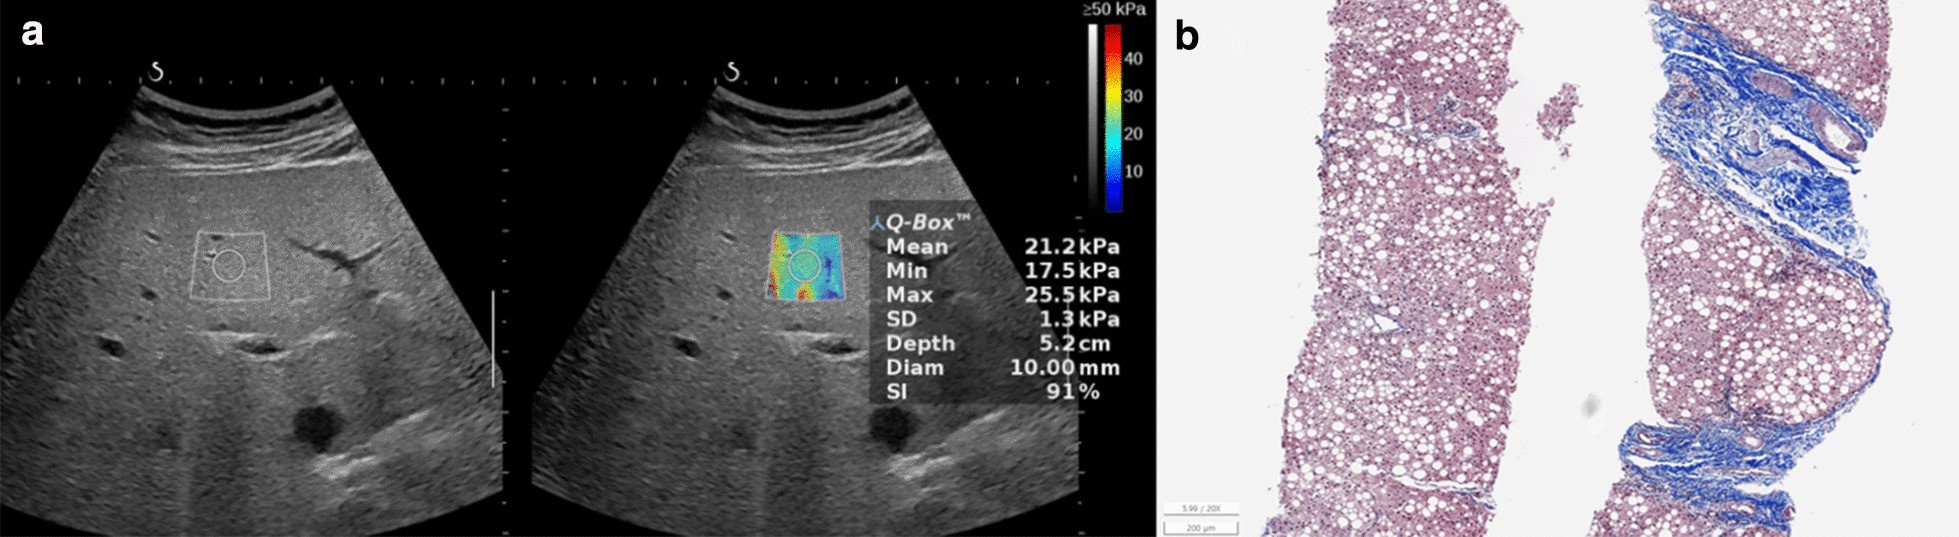

Fig. 4

Non-alcoholic fatty liver disease in a 13.9-year-old boy. The serum biochemical marker levels were as follows: AST to platelet ratio index (APRI), 1.3; AST to alanine aminotransferase ratio (AAR), 0.4; and fibrosis-4 (FIB-4) score, 0.4. a Two-dimensional shear-wave elastography (2D-SWE) showing diffuse hyperechoic parenchyma with 21.2 kPa liver stiffness value. b Histopathologic specimen showing mild necroinflammatory activity, severe macrovesicular steatosis, and significant septal fibrosis with architectural distortion with METAVIR score, F3